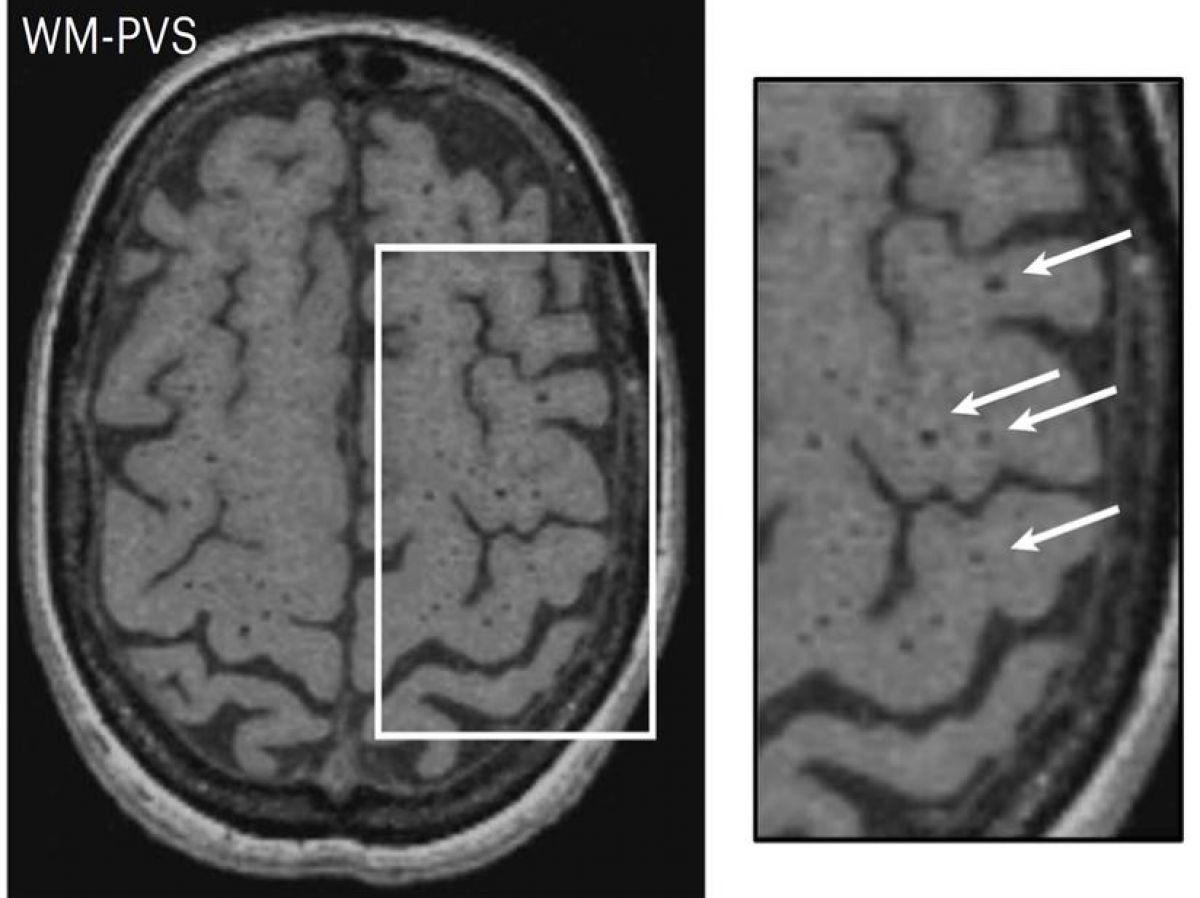

Espaces périvasculaires

Les chercheurs se sont ainsi focalisés sur les gènes impliqués dans l’apparition d’espaces périvasculaire (EPV). Les EPV sont des espaces physiologiques entourant les parois des petits vaisseaux sanguins dans le cerveau et permettant notamment l’élimination des déchets du cerveau. Détectables à l’IRM, ils constituent un des marqueurs IRM de la maladie des petites artères cérébrales permettant de la diagnostiquer avec d’autres altérations telles que les hypersignaux de la substance blanche, les infarctus lacunaires ou les microsaignements.